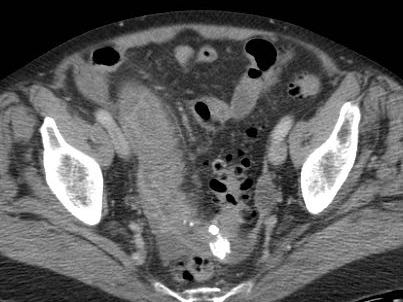

Ở bệnh nhân này, siêu âm cho thấy lượng lớn mô mỡ viêm (*) và hồi tràng dày thành, biểu hiện quá trình bao bọc thành công tình trạng thủng (sắp xảy ra) của ruột thừa (mũi tên).

Lưu ý sỏi phân vôi hóa (mũi tên trên CT) trong ruột thừa ở mức cao hơn.